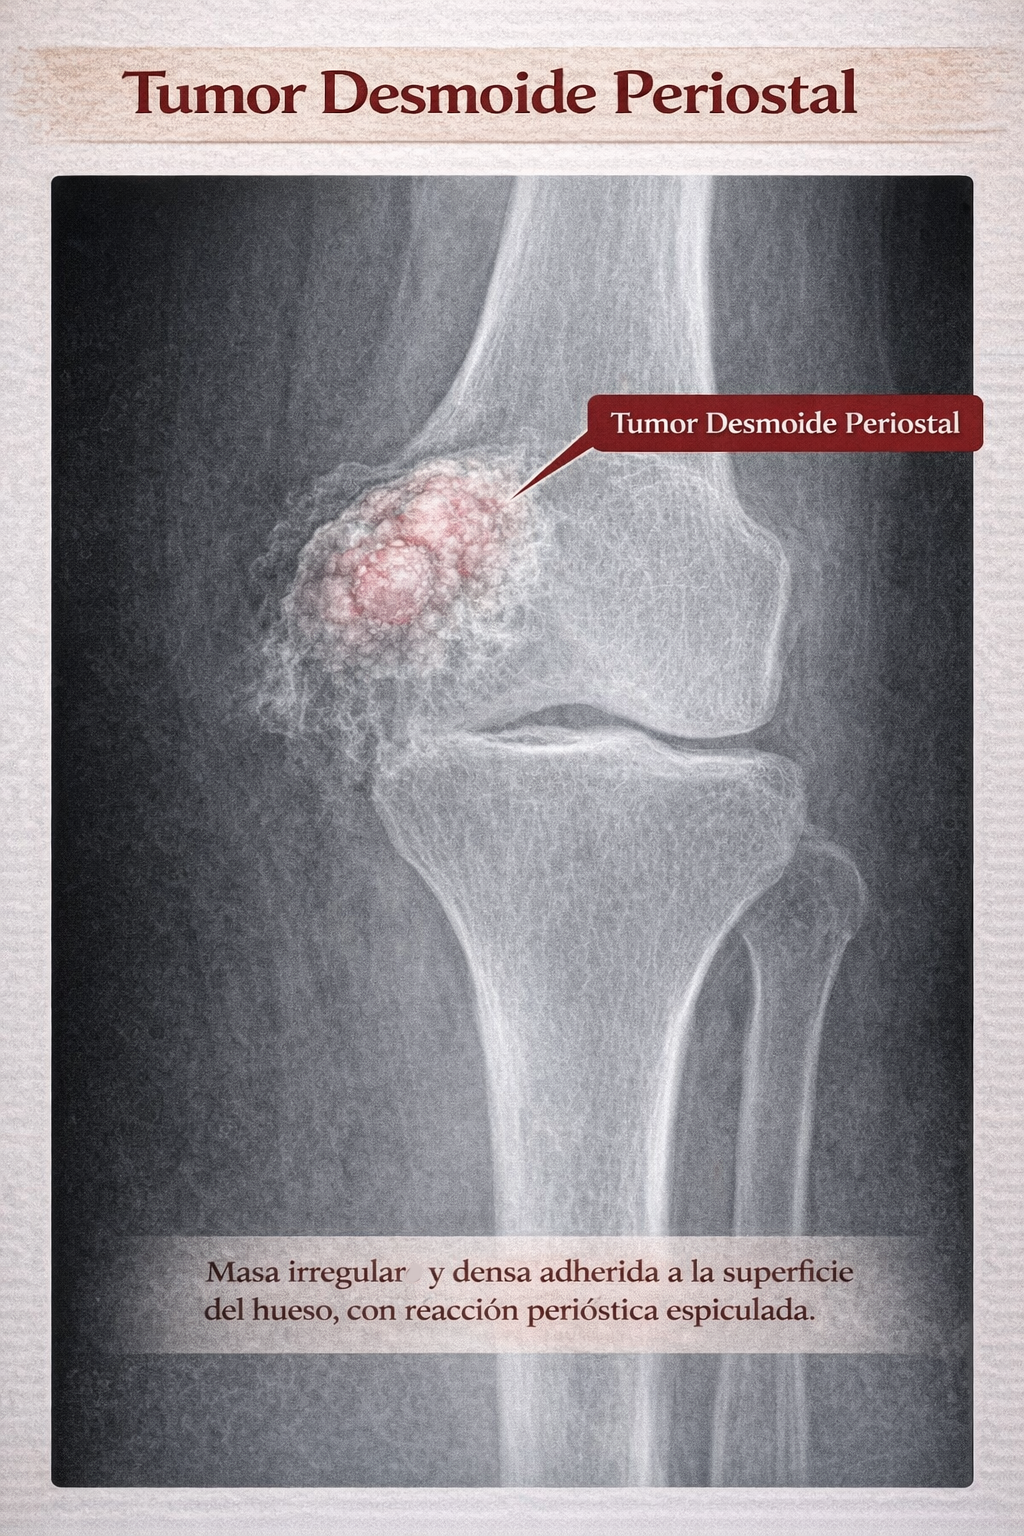

El desmoide periostal es una proliferación fibrosa benigna originada en el periostio y la cortical ósea, interpretada como una lesión por tracción (microavulsiones repetidas) en las inserciones musculotendinosas del fémur distal. No tiene comportamiento neoplásico y no debe confundirse con el tumor desmoide (fibromatosis agresiva) de partes blandas, que es una entidad completamente distinta.

Importante: no confundir con el “tumor desmoide” o “fibromatosis desmoide” de partes blandas, que es una entidad distinta con comportamiento localmente agresivo.

El diagnóstico diferencial del desmoide periostal incluye varias entidades que pueden presentarse como lesiones yuxtacorticales o corticales en el fémur distal. La localización típica y los hallazgos de imagen son los principales elementos para diferenciarlas: